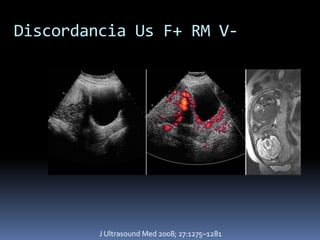

Discordancia Us F+ RM V-

J Ultrasound Med 2008; 27:1275–1281

Discordancia Us F+RM V- J Ultrasound Med 2008; 27:1275–1281